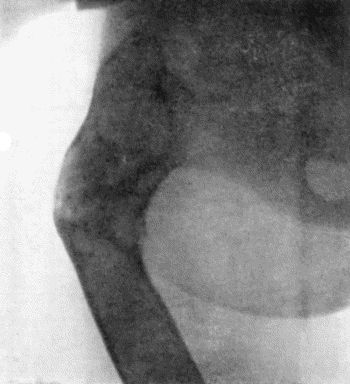

116.Great Enlargement of the Ischial Bursa 431

117.Gouty Disease of Bursæ 432